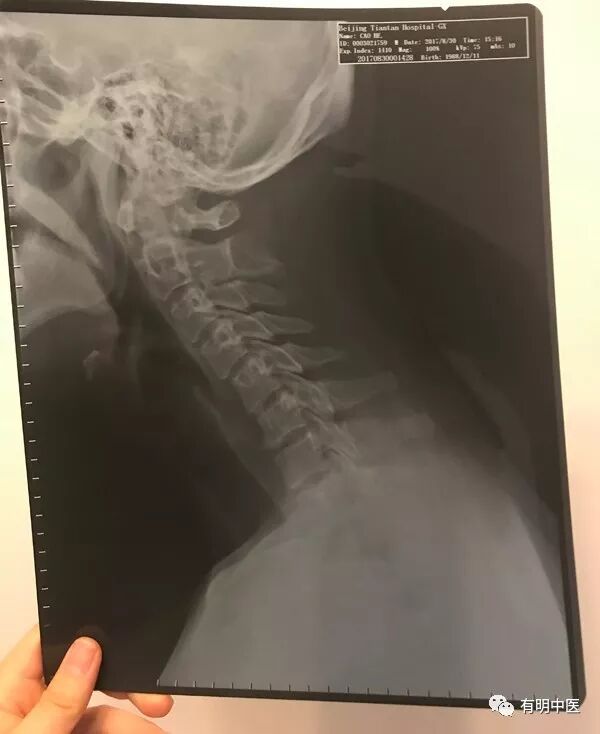

小曹的X光片

小曹来到了有明中医,罗院长看了他的片子,并进行的了病情的问诊,罗院长说:“片子上显示颈椎失稳,您是从事什么工作?”小曹说:“我从事的设计工作有4年了,每天对着电脑做图,脖子和眼睛就开始酸痛,没太在意,抗抗也就过去了。”罗院长说:“对着电脑的上班族,对着手机的低头族,尤其是整天保持一个姿势的像司机、教师等,患颈椎病的几率很高。你这情况。先治疗几次看看”。